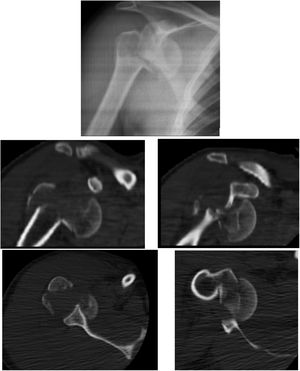

Reporte de casoMasculino de 35 años de edad quien ingresa al servicio de urgencias tras sufrir accidente de tránsito en motocicleta ocasionándole trauma en hombro derecho y rodillas bilaterales. Rayos X de ingreso se observa luxo fractura multifragmentada en 4 partes (Neer IV) en hombro derecho y fractura de platillos tibiales derecho (schatzker IV) (fig. 1), estatus neurológico normal, sin déficit neurovascular. Fracturas de manejo quirúrgico.

Se realizó reducción abierta de luxación escapulo humeral, osteosíntesis en húmero y reparación del manguito rotador del hombro derecho con una incisión deltopectoral de aproximadamente 20 centímetros que compromete piel y tejido celular subcutáneo; se realiza hemostasia del sangrado a nivel de capas, se hace una disección roma del músculo deltoideo dónde se pudo observar una fractura multifragmentaria de la cabeza del húmero proximal con luxación de la cabeza, se realiza apertura del manguito rotador a través del intervalo de los rotadores entre el subescapular y supraespinoso, disección roma hasta llegar a la cabeza del húmero, se hace reducción abierta de la luxación de la cabeza del húmero. Se realiza reducción abierta de la fractura de humero proximal fijándola inicialmente con 2 clavos Kirschner de 2.0mm, se realiza osteosíntesis con placa de humero proximal 9x3 utilizando 7 tornillos de bloqueo de 3.5mm y 3 tornillos corticales de 3.5mm, se sutura la interface del manguito rotador con suturas Parcus con puntos cruzados, se valora con intensificador de imagen dónde se observa una buena reducción y la cabeza del húmero en posición valga favoreciendo así su fijación (figs. 2 y 3).